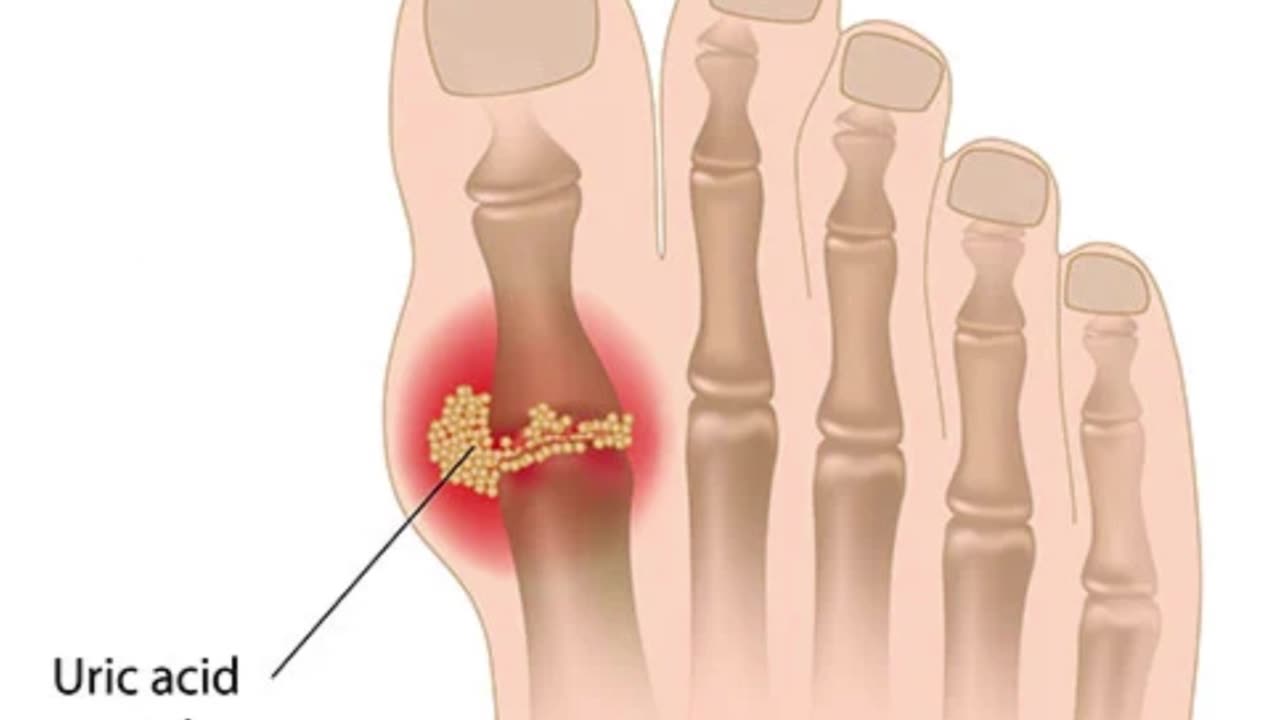

Can ginger really help with gout?

Ginger is well known for its natural anti-inflammatory properties, and research suggests it may help support uric acid balance and joint comfort.